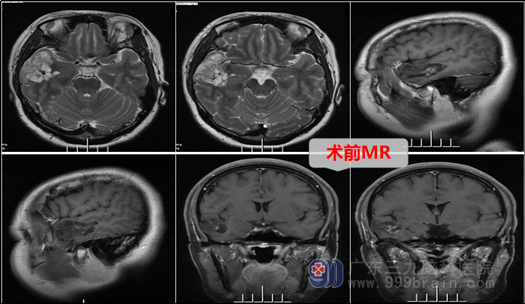

许多人都是在体检时偶然发现问题的,张某就是在体检时头颅MR发现“右侧颞叶占位性病变”,得知结果后就在想,自己平时没有头痛头晕,也没有恶心呕吐等其他不适,为进一步确诊,通过多方了解,在家人的陪同下来到广东三九脑科医院神经外十科就诊。

神经外十科欧阳辉教授接诊了张某,在了解详细病情后,结合患者外院MR,初步考虑“右侧颞叶肿瘤性病变”,欧阳教授向患者及其家属耐心解释病情及其预后,在征得患者及家属同意后,外十科团队在全麻下行右侧题叶低级别胶质瘤切除术+硬脑膜补片修补术+颅骨骨瓣修补术;全切肿瘤,手术顺利。术后患者神志清楚,病理诊断为:神经原性一级肿瘤(良性),患者术后也没有出现后遗症。